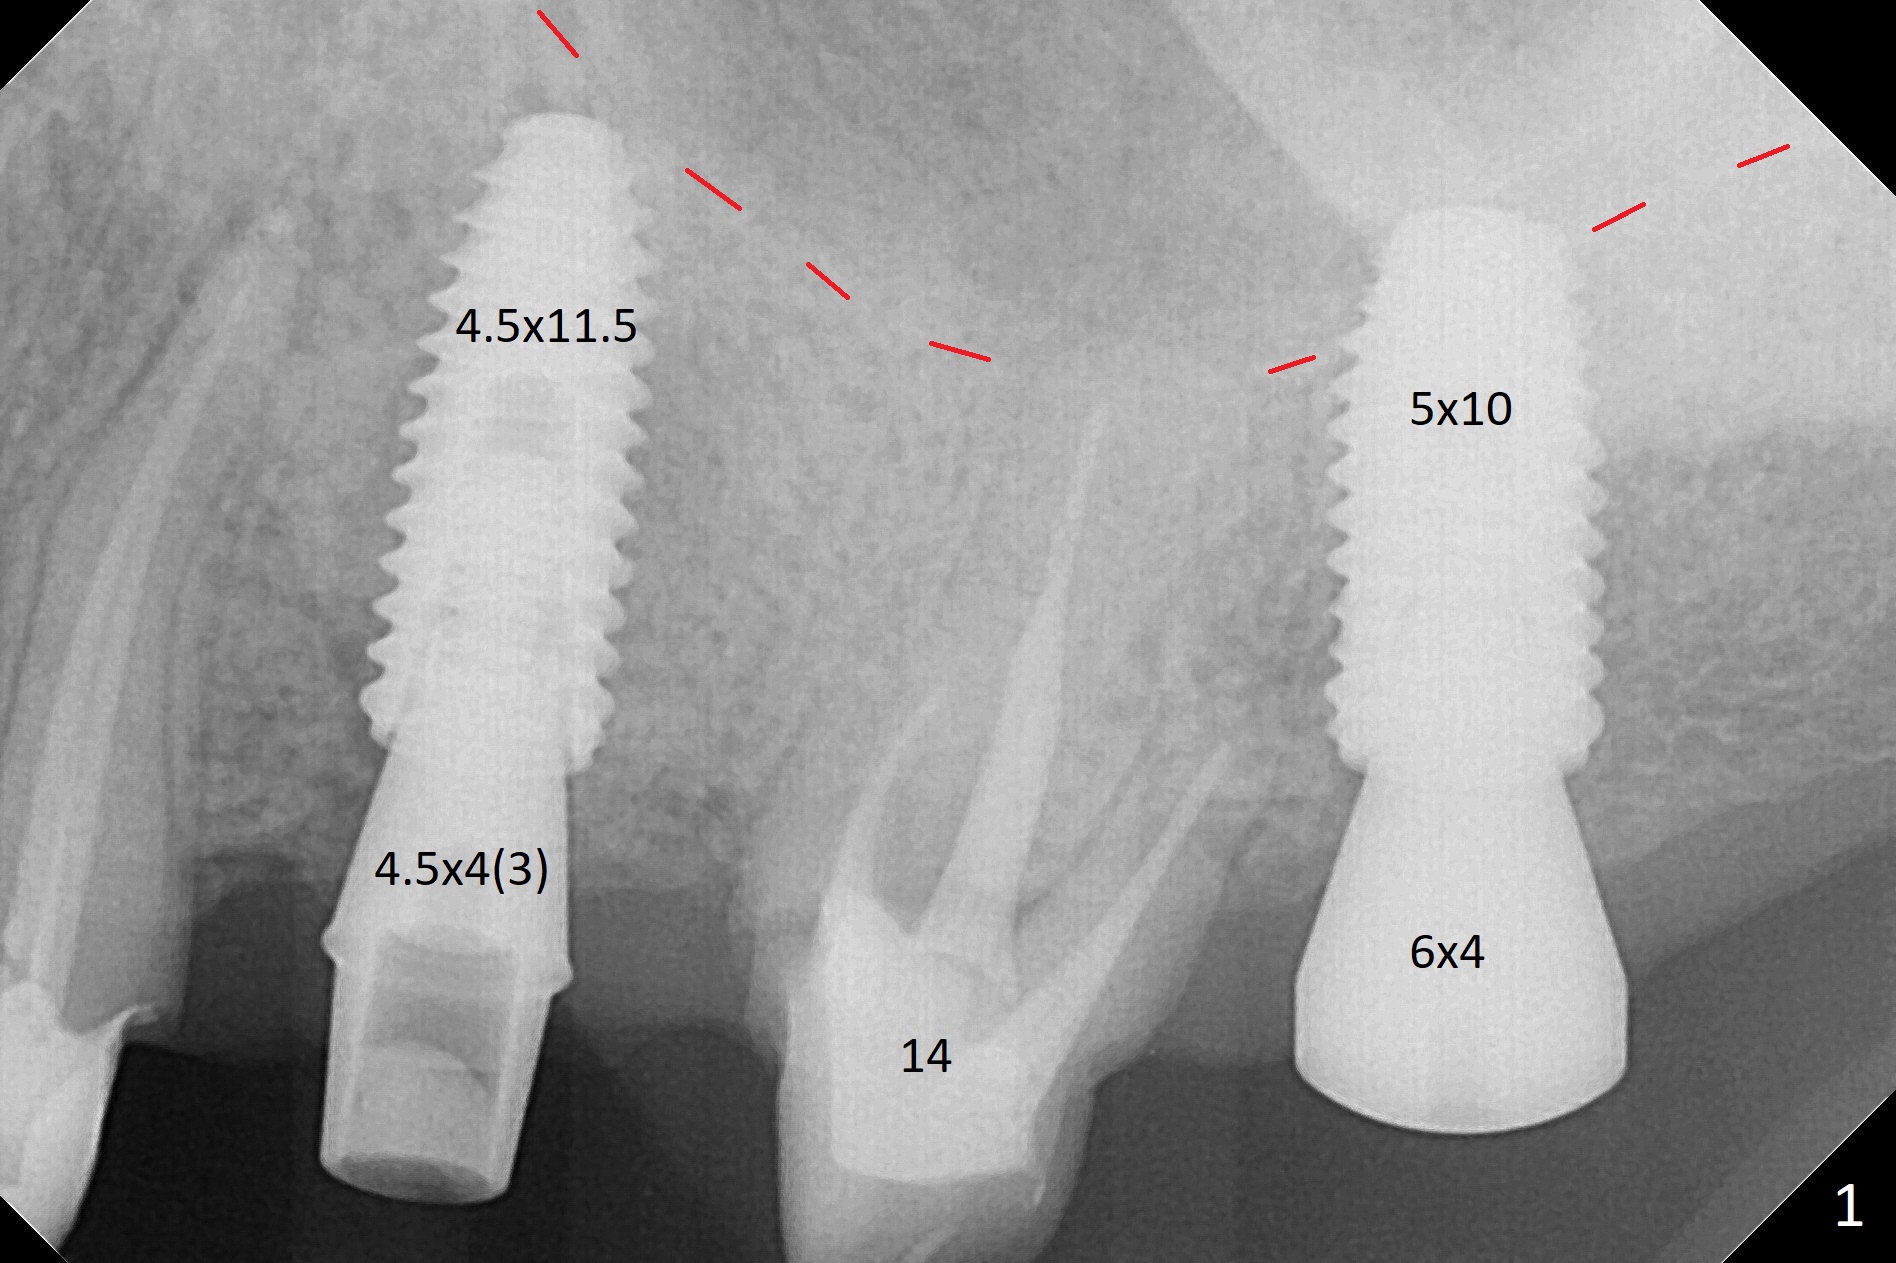

After underdrilling (3.5x14.5 mm drill (10.5 mm offset), a 4.5x11.5 mm implant is unable to enter the osteotomy at #13; following use of 4x10 mm drill (partial normal drilling), the implant is inserted smoothly with insertion torque ~ 35 Ncm. Sticky bone is placed in the bony portion of the buccal gap, while 2 pieces of PRF membrane in the gingival portion of the buccal gap. The bone density at #15 is low, the insertion torque is ~15 Ncm with normal drilling without cortical tap (Fig.1). The procedure is smooth in part due to no sinus involvement (red dashed line). An immediate provisional FPD is fabricated for #12-14. But local oral hygiene is difficult to maintenance. When the wound heals at #13, the FPD is removed. The bone loss is minimal nearly 4 months postop; the abutment at #13 is incompletely seated (Fig.2 arrowheads: gap). After repositioning, the abutment is re-seated completely without gap (arrowheads); a 5.7x4(3) mm cemented abutment is placed at #15 (Fig.3,4). Four crowns are cemented 4 months 10 days postop (Fig.5).